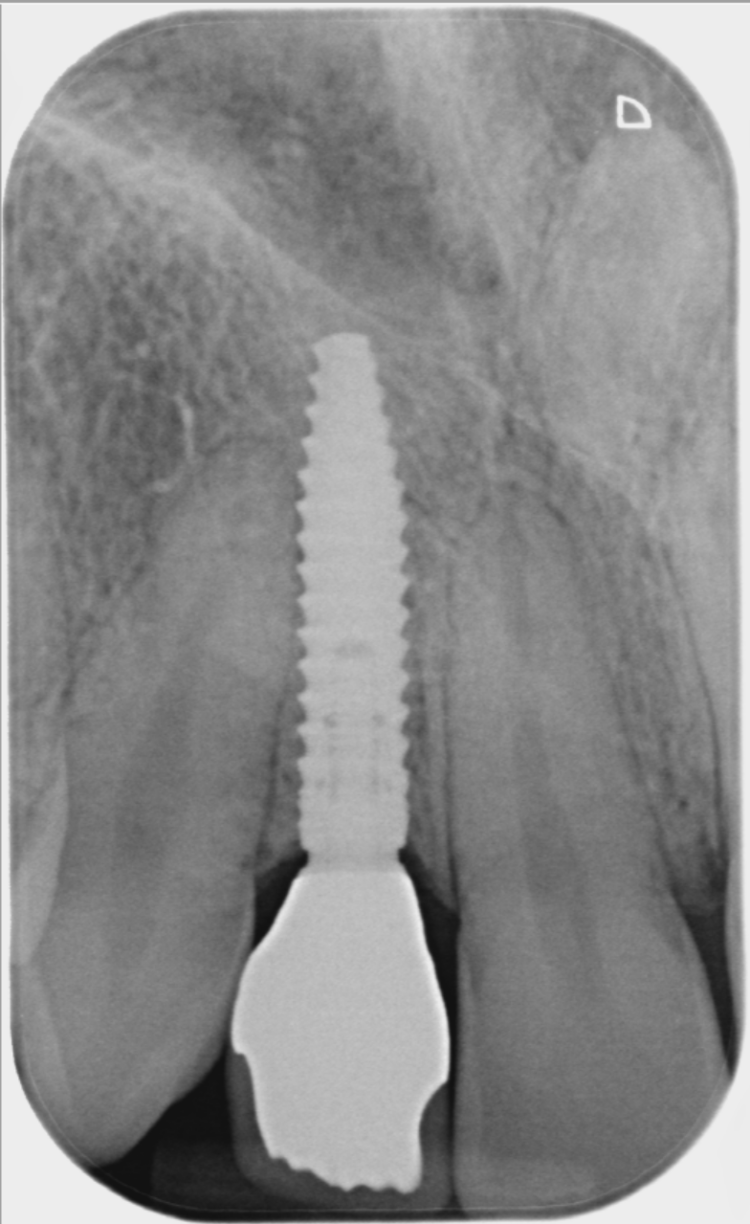

A CBCT scan was taken using a Morita X800. This dataset was imported into the planning software, where it was merged with the STLs of the anatomically correct diagnostic digital wax-up and modules.  With the anatomically correct diagnostic wax-up, there was no ambiguity regarding planning the implant position, angle and depth with precision. I like to plan these types of cases myself, but it is possible to outsource the planning stage for clinicians who are new to the process and looking to increase their workflow efficiency. For this case, I wanted to build up the gingival thickness in order to improve the papillae around the implant sites. The surgical plan, therefore, included soft tissue grafting.

On the day of surgery, a split-thickness envelope flap was raised. Two CONELOG® Progressive-Line implants were placed through the surgical guide in the pre-determined lateral incisor positions. Soft tissue augmentation was performed simultaneously with the implant placement, and the site was sutured and closed without tension. The implants were immediately loaded using provisional crowns that were pre-fabricated in the lab.

The CONELOG implants were selected because they provide a very stable connection and feature a geometry that facilitates high primary stability, which is important when placing immediate implants. They also integrate very successfully – we have had better results with these implants than with other products that are available. I also appreciate the simplicity of the keyless guided surgery kit.